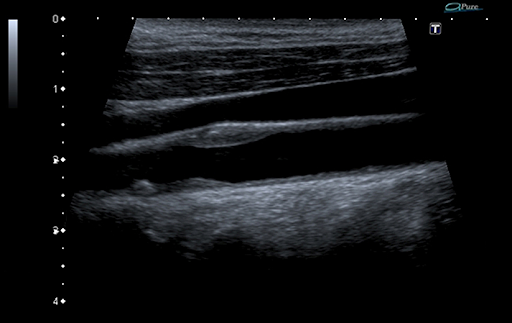

Auto-IMT - это удобный и простой в использовании инструмент для автоматизации измерения толщины интима-медиа (IMT) проксимальных и дистальных стенок артерий. Данная технология незаменима для определения риска сердечно-сосудистых заболеваний у пациента.